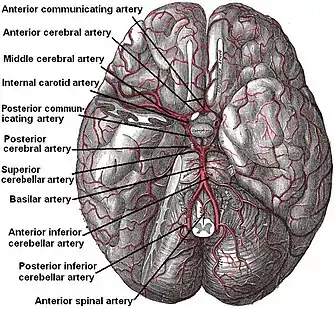

| |

| Circle of Willis Arteries beneath brain | |

- Focal cerebral ischemia – A stroke occurring in a localized area that can either be acute or transient. This may be due to a variety of medical conditions such as an aneurysm that causes a hemorrhagic stroke, or an occlusion occurring in the affected blood vessels due to a thrombus (thrombotic stroke) or embolus (embolic stroke).[21] Focal cerebral ischemia constitutes a large majority of the clinical cases in stroke pathology with the infarct usually occurring in the middle cerebral artery (MCA).[22]